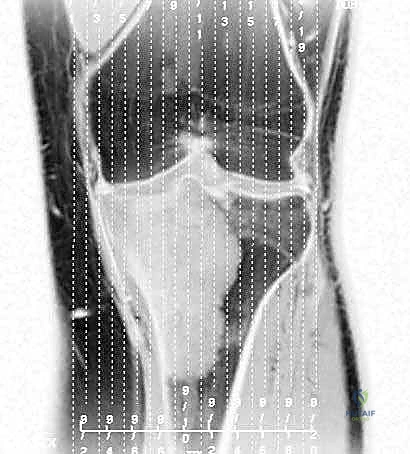

يقع المفصل الظنبوبي الشظوي القريب بالقرب من الجانب الخلفي الوحشي (الخارجي) للظنبوب القريب، وهو يربط بين عظم الظنبوب وعظم الشظية. تُظهر الدراسات النسيجية والباثولوجية المتقدمة أن الأورام الخبيثة التي تصيب الظنبوب القريب غالباً ما لا تحترم الحدود التشريحية، وتمتد لتشمل الأنسجة المحيطة بهذا المفصل الصغير.

لذلك، وفي قاعدة جراحية ذهبية للحصول على "هامش جراحي آمن" (Safe Surgical Margin) وخالٍ تماماً من الخلايا السرطانية، من الضروري إزالة هذا المفصل بالكامل كوحدة واحدة (En Bloc Resection) مع الظنبوب المصاب وعظم الشظية القريب. هذه العملية تُعرف بالاستئصال خارج المفصل (Extra-articular Resection)، وهي تضمن عدم ترك أي خلايا ورمية مجهرية قد تؤدي إلى انتكاس المرض وعودته في المستقبل.

* ورم الخلايا العملاقة (Giant Cell Tumor - GCT): هو المثال الأبرز في هذه الفئة. ينشأ غالباً في نهايات العظام الطويلة بالقرب من المفصل (مثل الظنبوب القريب). في الحالات المتقدمة التي يدمر فيها الورم القشرة العظمية وسطح المفصل، يصبح الاستئصال الكامل وإعادة البناء بالطرف الصناعي هو الخيار الأمثل لمنع عودة الورم (Recurrence).